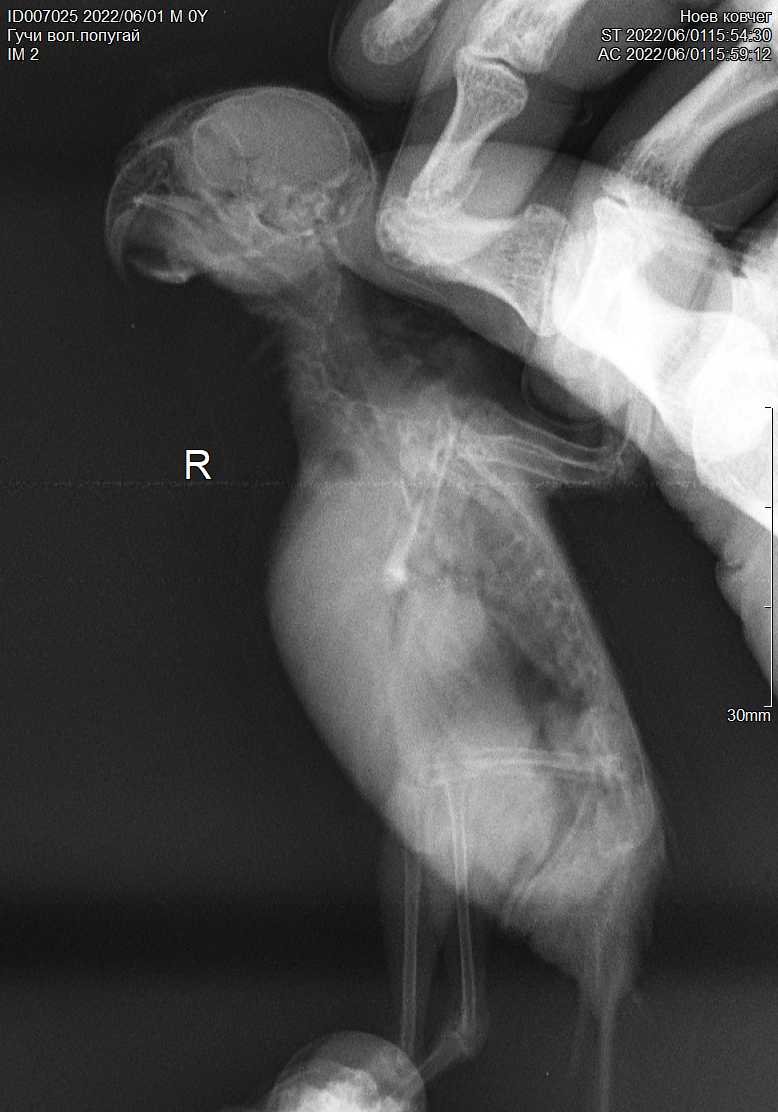

5. Здравствуйте! Решила все-таки создать тему про лечение птицы из этого поста. У нас, помимо физических повреждений, нашли ещё кучу всего. Вообще бедный птен, похоже, пока его не подобрали, с поврежденным крылом и лапкой еще неделю на улице выживал, питаясь непонятно чем и подмерзая( Полный список диагнозов пока: кандидоз, кокцидиоз, трихомоноз (хотя наростов нет, но нашли трихомонаду в анализе кала), гепатоз (на рентгене печень очень сильно увеличена, как сказали, может быть результатом трихомоноза как раз), аэросаккулит (под вопросом). Плюс вывих правого плечевого сустава и закрытый перелом бедра. Назначили лечение: 1. Флуконазол 50 мг ? капсулы в 1 мл воды, выпаивать по 0,3 2 р.д. 14 дней. 2. Мелоксикам 7,5 мг ? таблетки в 1 мл воды выпаивать по 0,6 2 р.д. после еды 3. Гептрал или Самеликс 1/10 таблетки с едой 4. Стоп-кокцид 2,5% 0,18 мл однократно (уже дали, на следующей неделе повторно сдадим анализ) 5. Амоксиклав суспензия по 0,4 мл 2 р.д. 14 дней (подключить на след. неделе) 6. Метрогил 5 мг/мл 0,5 мл 2 р.д. + витамины и кальция глюконат Сдали анализы на псевдотуберкулез, хламидиоз, микоплазмоз и сальмонеллез. Первые три все пришли отрицательные, последний еще ждем, но его сдавали скорее для галочки – помет не сальмонельный и особых подозрений на нее и не было. Не смотря на такой букет, птиц достаточно активный и бодрый, первое время, конечно, лежал-боялся, сейчас осмелел, чистит перья, делает зарядку и отчаянно пытается урчать и бить меня крылом, стоит мне полезть к нему, чтобы покормить, поменять подстилку или дать лекарства. Вопросы у меня такие: лечение кажется адекватным, но прям очень много всего… не добьем ли мы так печень окончательно, даже под прикрытием гептрала? К тому же меня сильно беспокоит вес птички… когда подобрали, он был 230 грамм. При последнем взвешивании – 220. При этом ест птица сама и хорошо (хотя сейчас и не так жадно, как первые дни), еда, судя по анализам, переваривается, и зерно из зоба уходит, хотя и чуть медленнее, чем должно быть – за часа 3-3,5. Так почему худеет? Это следствие инфекций и нужно сперва бороться с ними и тогда вес сам наладится? Или стоит докармливать, пусть даже и насильно? Ну и вообще – может, будут какие-то общие рекомендации? И какие вообще шансы у птицы с таким набором всего? P.S.: Прилагаю фото птички и помета. Всё снято сегодня. Чуть позже попробую приложить рентген, если смогу открыть диск.